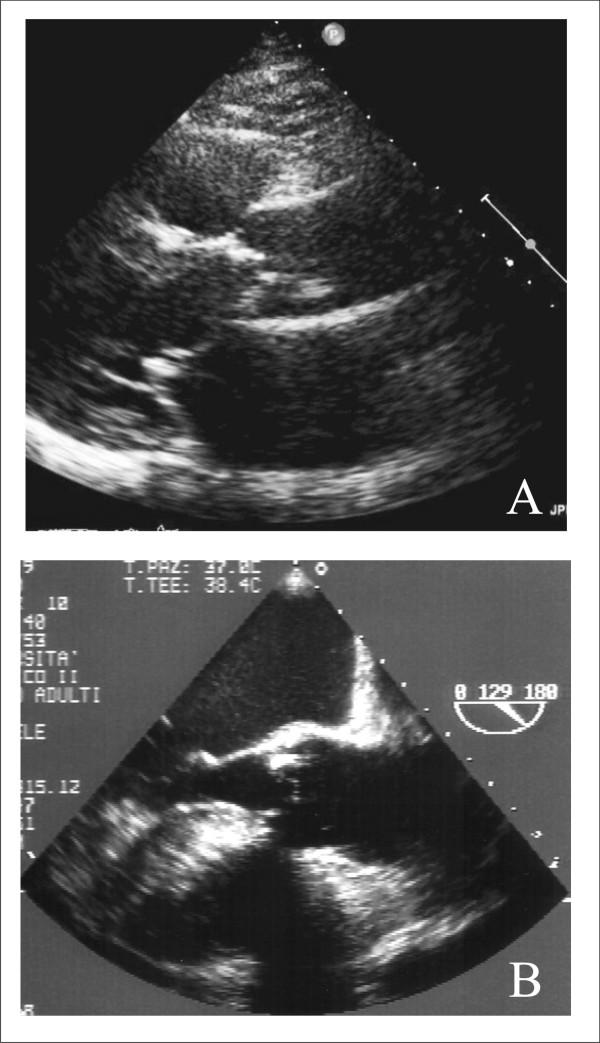

Aortic stenosis and mitral regurgitation, patent foramen ovale, interatrial septal defect, atrial fibrillation and perivalvular leak, are now amenable to percutaneous treatment. These percutaneous procedures require the use of Transthoracic (TTE), Transesophageal (TEE) and/or Intracardiac echocardiography (ICE). This paper provides an overview of the different percutaneous interventions, trying to provide a systematic and comprehensive approach for selection, guidance and follow-up of patients undergoing these procedures, illustrating the key role of 2D echocardiography.

主动脉瓣狭窄、二尖瓣反流、卵圆孔未闭、房间隔缺损、心房颤动及瓣周漏,目前均适合经皮治疗。这些经皮手术需要使用经胸超声心动图(TTE)、经食管超声心动图(TEE)和/或心内超声心动图(ICE)。本文概述了不同的经皮介入治疗,试图为接受这些手术的患者提供一种系统、全面的选择、指导及随访方法,并阐述二维超声心动图的关键作用。